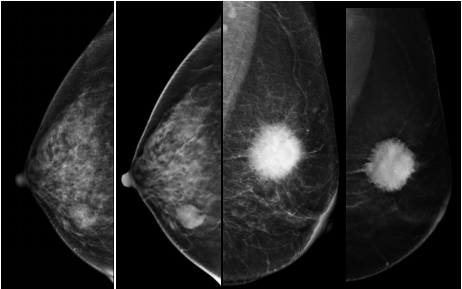

是利用不同投射角度重建出与探测器平面平行的任意层面乳腺三维X线影像,通过一次投照给出一系列类似CT图片的断层图像,可有效降低了腺体组织重叠的影响,提高了致密型乳腺疾病的检出率。

第1、3图片为数字乳腺摄影,第2、4张图片为数字断层摄影,明显数字断层摄影图片对病灶的边界显示更清楚,更有利于医生对良恶性病灶的定性及分级。